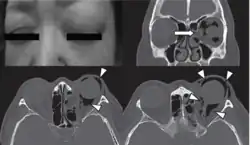

| Woman with preorbital swelling in orbital emphysema shown in CT scans | |

Computed tomography (CT)

Computed tomography is effective and sensitive in the diagnosis of orbital emphysema,[3][37] as it can confirm the anatomical location and size of air, bony defects, indentation of the eyeball, and the condition of the optic nerve, as well as the presence of any extraocular muscle entrapment and herniation of preorbital fat into the sinus cavities.[3][15][38] The location of the orbital emphysema is present near the site of the fracture.[1][3] The scans are usually taken along the transverse plane. Transverse images allow the evaluation of fractures in medial and lateral orbital walls. By reformatting these transverse images or taking coronal images, the examination of orbital floor and roof is permitted. Helical scanning is preferred as it has a lower imaging time and radiation dose comparing to conventional scanning, especially when reforming transverse helical scans into coronal images.[3] The staging of orbital emphysema can then be determined with visual acuity examination and ophthalmoscopy.[6] A disadvantage of using a CT scan is that when detecting air after orbital trauma, the presence of a wooden foreign object can give a false positive result of orbital emphysema. The wooden object can mimic the presence of orbital emphysema. Therefore, patients’ medical history is crucial in making the correct diagnosis.[3]